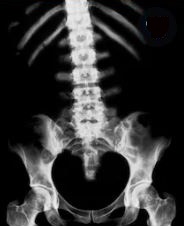

病名は「変形性腰椎症」とのこと・・背骨が左に曲がっているらしい・・

イメージは↓